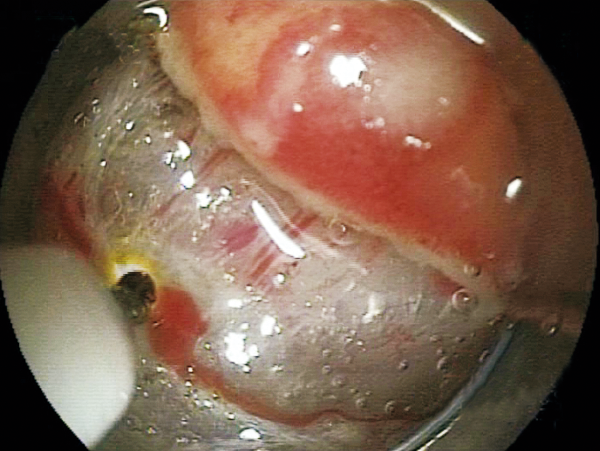

One knife covers 6 major functions for ESD, achieving high versatility

Able to incise the target tissue smoothly from side to side and up to down.

The variation of the tip type and length realizes the optimal approach for each lesion and technique.